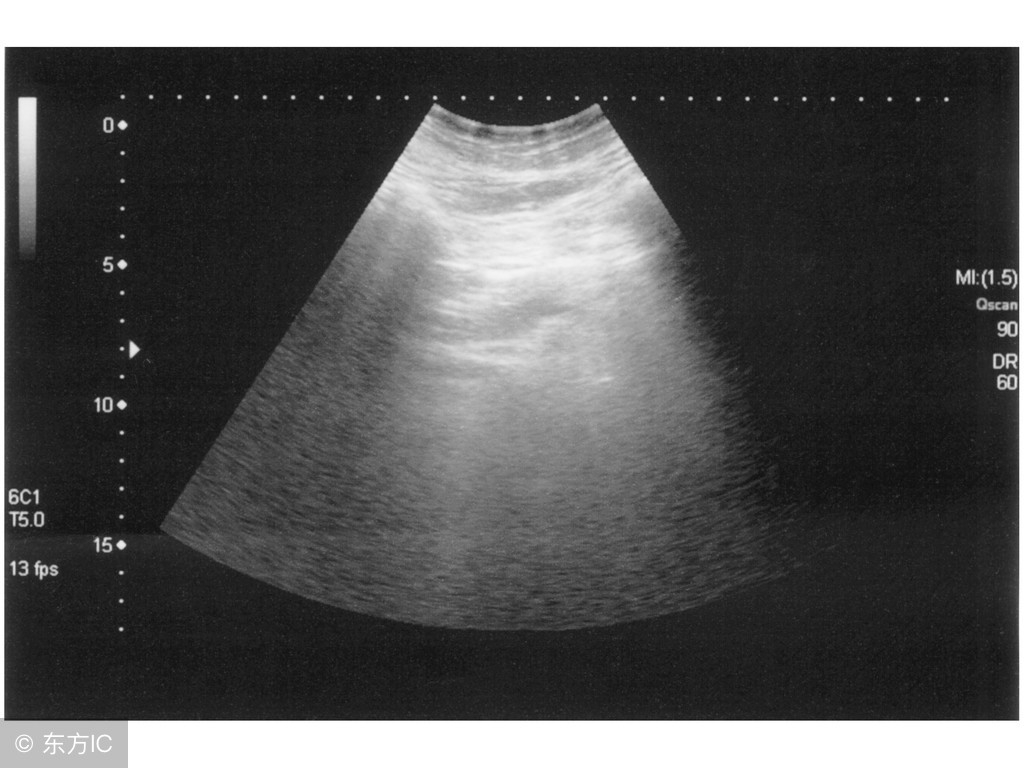

3、最好的区分的方法当然是去医院做检查了,最实用的方法做B超和做胃镜,做B超不仅可发现结石、结石的大小、移动与否和周围组织关系,还可以了解胆道的功能以及胆结石与胆囊息肉、肝病的区别;而胃镜对胃的情况做出较准确的诊断,所以,做了检查就能区分这两个病了!